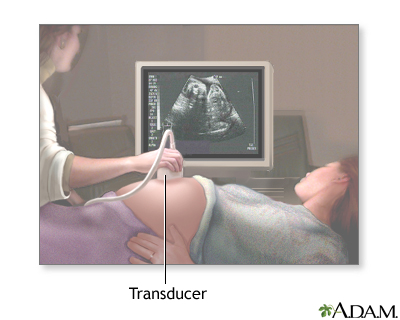

An ultrasound machine makes images so that organs inside the body can be examined. The machine sends out high-frequency sound waves, which reflect off body structures. A computer receives the waves and uses them to create a picture. Unlike with an x-ray or CT scan, this test does not use ionizing radiation.

- A clear, water-based gel is applied to the skin on the area to be examined. The gel helps with the transmission of the sound waves.

- A handheld probe called a transducer is moved over the area being examined. You may need to change position so that other areas can be examined.